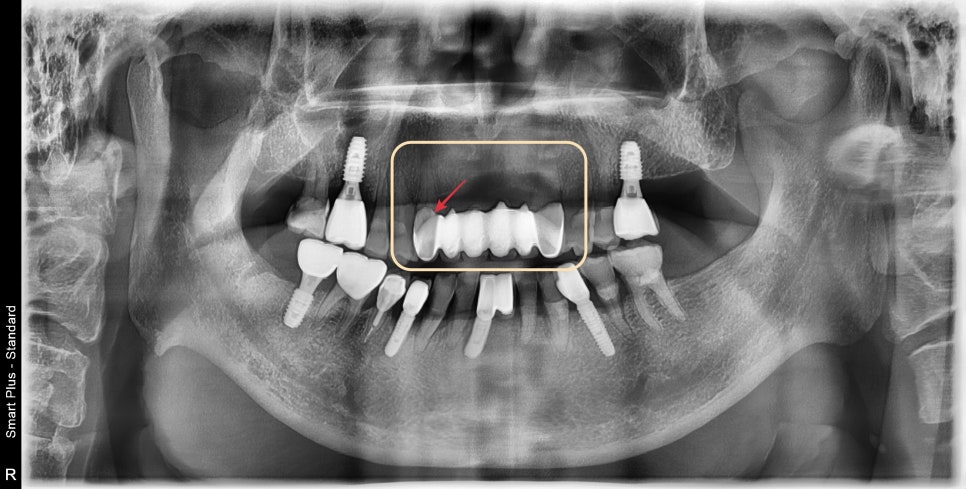

검진 결과 화살표로 표시된 부분의 치아머리 부분이 부러져 있었습니다.

양쪽 송곳니 2개의 치아로 장기간 동안 6개의 치아의 힘을 견딘 것이 주된 원인이었습니다

반대편 송곳니도 이미 동요 도도 관찰되고 있는 상황에서 재보철은 어렵다고 판단

임플란트가 적합한 치료방법이라고 설명해 드렸습니다.

어금니가 하나씩 부족하시고

평소 교합력이 많이 강하신편이기 때문에 상악 6개의 앞니를 버티기 위해서는

4개 정도가 튼튼하지만 뼈의 상태를 평가했을 때 3개의 임플란트가 최선이었습니다.